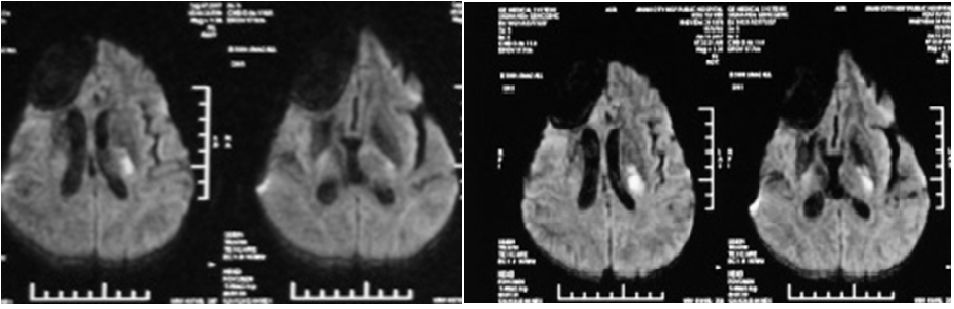

2017年6月与9月颅脑MR